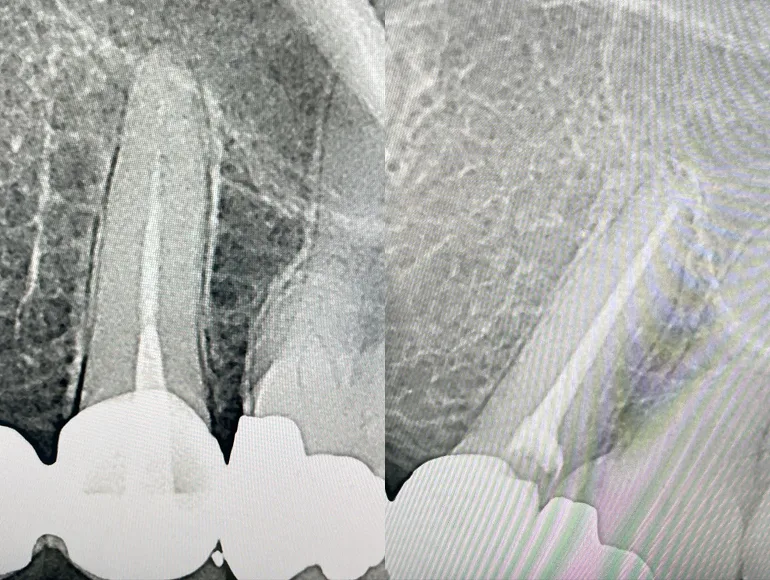

Rootcanal therapy through dental prosthesis

Case by Dr. Taha Azimaie: Retreatment of rootcanal through dental prosthesis can save patient money and dental visits. This tooth endodontically treated and was part of a dental bridge. The tooth also contained a long pin (AKA post) that is cemented deep in the canal, removal of a post is a challenging procedure and can lead to tooth fracture. In this case, an access hole made through the bridge and post removed. Root canal therapy retreated and the access hope filled with dental filling material. Now this dental bridge can last longer and may not require replacement.